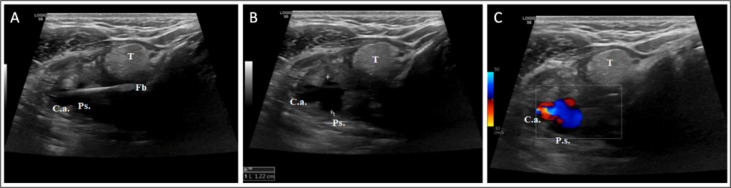

Carotid complications resulting from extra-luminal migration of ingested foreign bodies (FB) are rare but potentially life-threatening. Previous data on the topic predominantly comprises isolated case reports, leaving a gap in comprehensive evidence necessary to guide clinical decision-making. In this article, we offer a narrative review alongside a novel case report, aimed at providing a broad, evidence-based perspective on the topic to guide clinical practice. The search strategy employed keywords related to carotid artery complications from ingested FB across the following electronic databases: PubMed, Scopus, Google Scholar, and Cochrane Central. Screening involved standardized data extraction by two independent reviewers, with a focus on abstracts meeting inclusion criteria and excluding non-English literature and non-relevant studies from further analysis. Moreover, we present a novel case report on the topic that was successfully managed using a unique surgical approach. Overall, a total of sixteen case reports were finally included, data on clinical presentations, diagnostic strategies and findings, surgical management and outcome were extracted, tabulated, and discussed. In carotid complications from extra-luminal migration of ingested FB, high clinical suspicion is crucial due to potentially mild symptoms and negative first-level examinations. Computed tomography (CT) scan plays a pivotal role for accurate diagnosis and surgical planning, along with neck ultrasound to detect complications. Tailored surgical strategies based on the severity of carotid involvement, including venous patch grafts in severe vessels involvement, are crucial for optimal patient outcomes. As a novelty, in our case report, carotid shunt was successfully employed instead of prolonged carotid clamping to reduce the risk of associated neurological sequelae. It could be concluded that, diagnosis and managing carotid complications from extra-luminal migration of ingested FB remains challenging and a multidisciplinary approach is warranted.